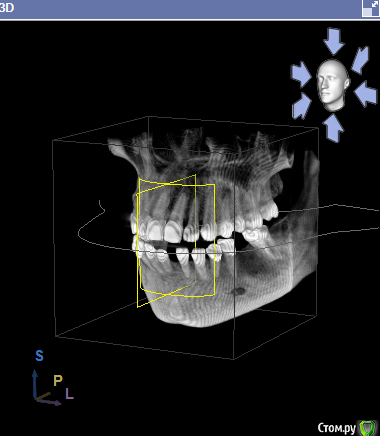

svetanik8 Опубликовано 25 мая, 2017 Поделиться Опубликовано 25 мая, 2017 Уважаемые врачи, прошу совета, чтобы определиться с тем, что делать.Году на 28м узнала, что у меня неправильный прикус (прямой), с детства отсутствует нижний передний зуб (детская травма, на тот момент врачи сказали, что зубы сойдутся, все будет ок, не сошлись, но мало кто видит, что его нет, улыбка как бы не такая низкая, чтобы открывать нижний ряд зубов).Лет в 25 удалили первую 6ку в нижнем ряду, спустя пару лет вторую симметрично, итого имею три проблемы, которые нужно решить (имплантация либо мост). Посетила пару врачей, один ортодонт предложил установить брекеты только на несколько нижних зубов с тем, чтобы сделать место для импланта на месте отсутствующего переднего, так как прикус меня 30 лет до этого не беспокоил, мне зубы кажутся ровными. Врач имплантолог в этой же клинике предложил по всем трем отсутствующим зубам сделать какое-то расщепление с подсадкой, при котором сразу же ставится имплант, причем обе шестерки предложил объединить в одну операцию, чтобы сэкономить на какой-то мембране.Второй врач сказал делать подсадку ткани по всем трем, по брекетам ничего не прокомментировал, отдельно нужно общаться с ортодонтом.И еще один врач тоже сказал, что нужно делать подсадку костной ткани, что расщепление ему не очень нравится в принципе, что может отломаться кость и тп. Подсадка костной ткани очень недешевая процедура (или я ходила в такие клиники дорогие, не знаю). Вопрос, стоит ли в моем случае делать импланты (по каждому зубу) или где-то лучше мост (например, семерка слева под коронку уже, там ползуба нет).Прилагаю снимки ОПТГ и КТ (скриншоты, если нужны другие ракурсы скажите, пока не разобралась как их делать).Отдельный вопрос по брекетам, не знаю выносить ли в отдельнуютему, проблема комплексная. На всякий случай еще фото обычные зубов.Спасибо заранее. Ссылка на комментарий